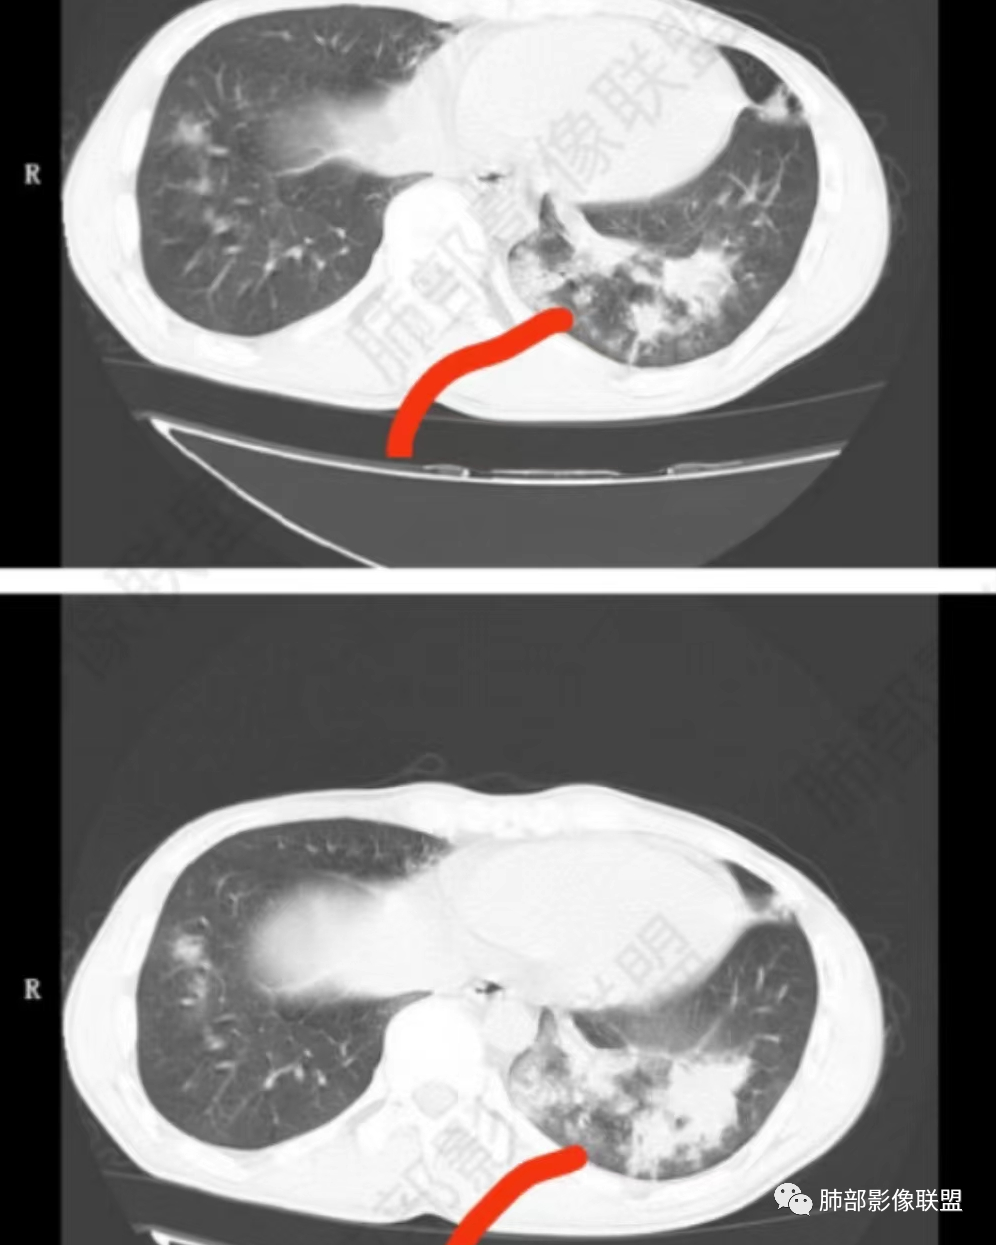

2021-7-14

2021-8-28

右肺中叶及左肺舌叶支气管扩张,双肺下叶斑片,小片状影伴磨玻璃影,边缘部分模糊。炎性指标不高,血糖略高,考虑支扩合并真菌感染。NTM。

男,21,咳嗽伴左胸壁痛2天。胸部CT:右中叶、左舌叶支气管扩张,双肺下叶斑片影,左下多发,沿支气管束分布,小片状影伴磨玻璃影,边缘模糊,树雾?考虑支扩合并感染,支原体?NTM?鉴别ABPA、CPAM、隔离等。

2、影像特点:右肺中叶、左肺下舌段可见支扩。左肺下舌段及两肺下叶可见片状实变影及发结节影,病灶边界多显示不清,纵隔窗显示病灶密度较均匀,未见液化、空洞或钙化。左肺下叶部分病灶沿支气管分布,并可见局部支气管管壁增厚。